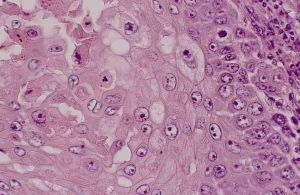

表皮角化,腫瘤由鱗狀上皮細胞團塊所組成,不規則地向真皮內浸潤,棘細胞呈瘤性增生,呈條索狀或巢狀細胞團,邊緣以基底細胞層,中心部有角化性癌珠,在癌細胞團內有很多分裂象,周圍淋巴細胞和漿細胞浸潤。上皮組織實驗